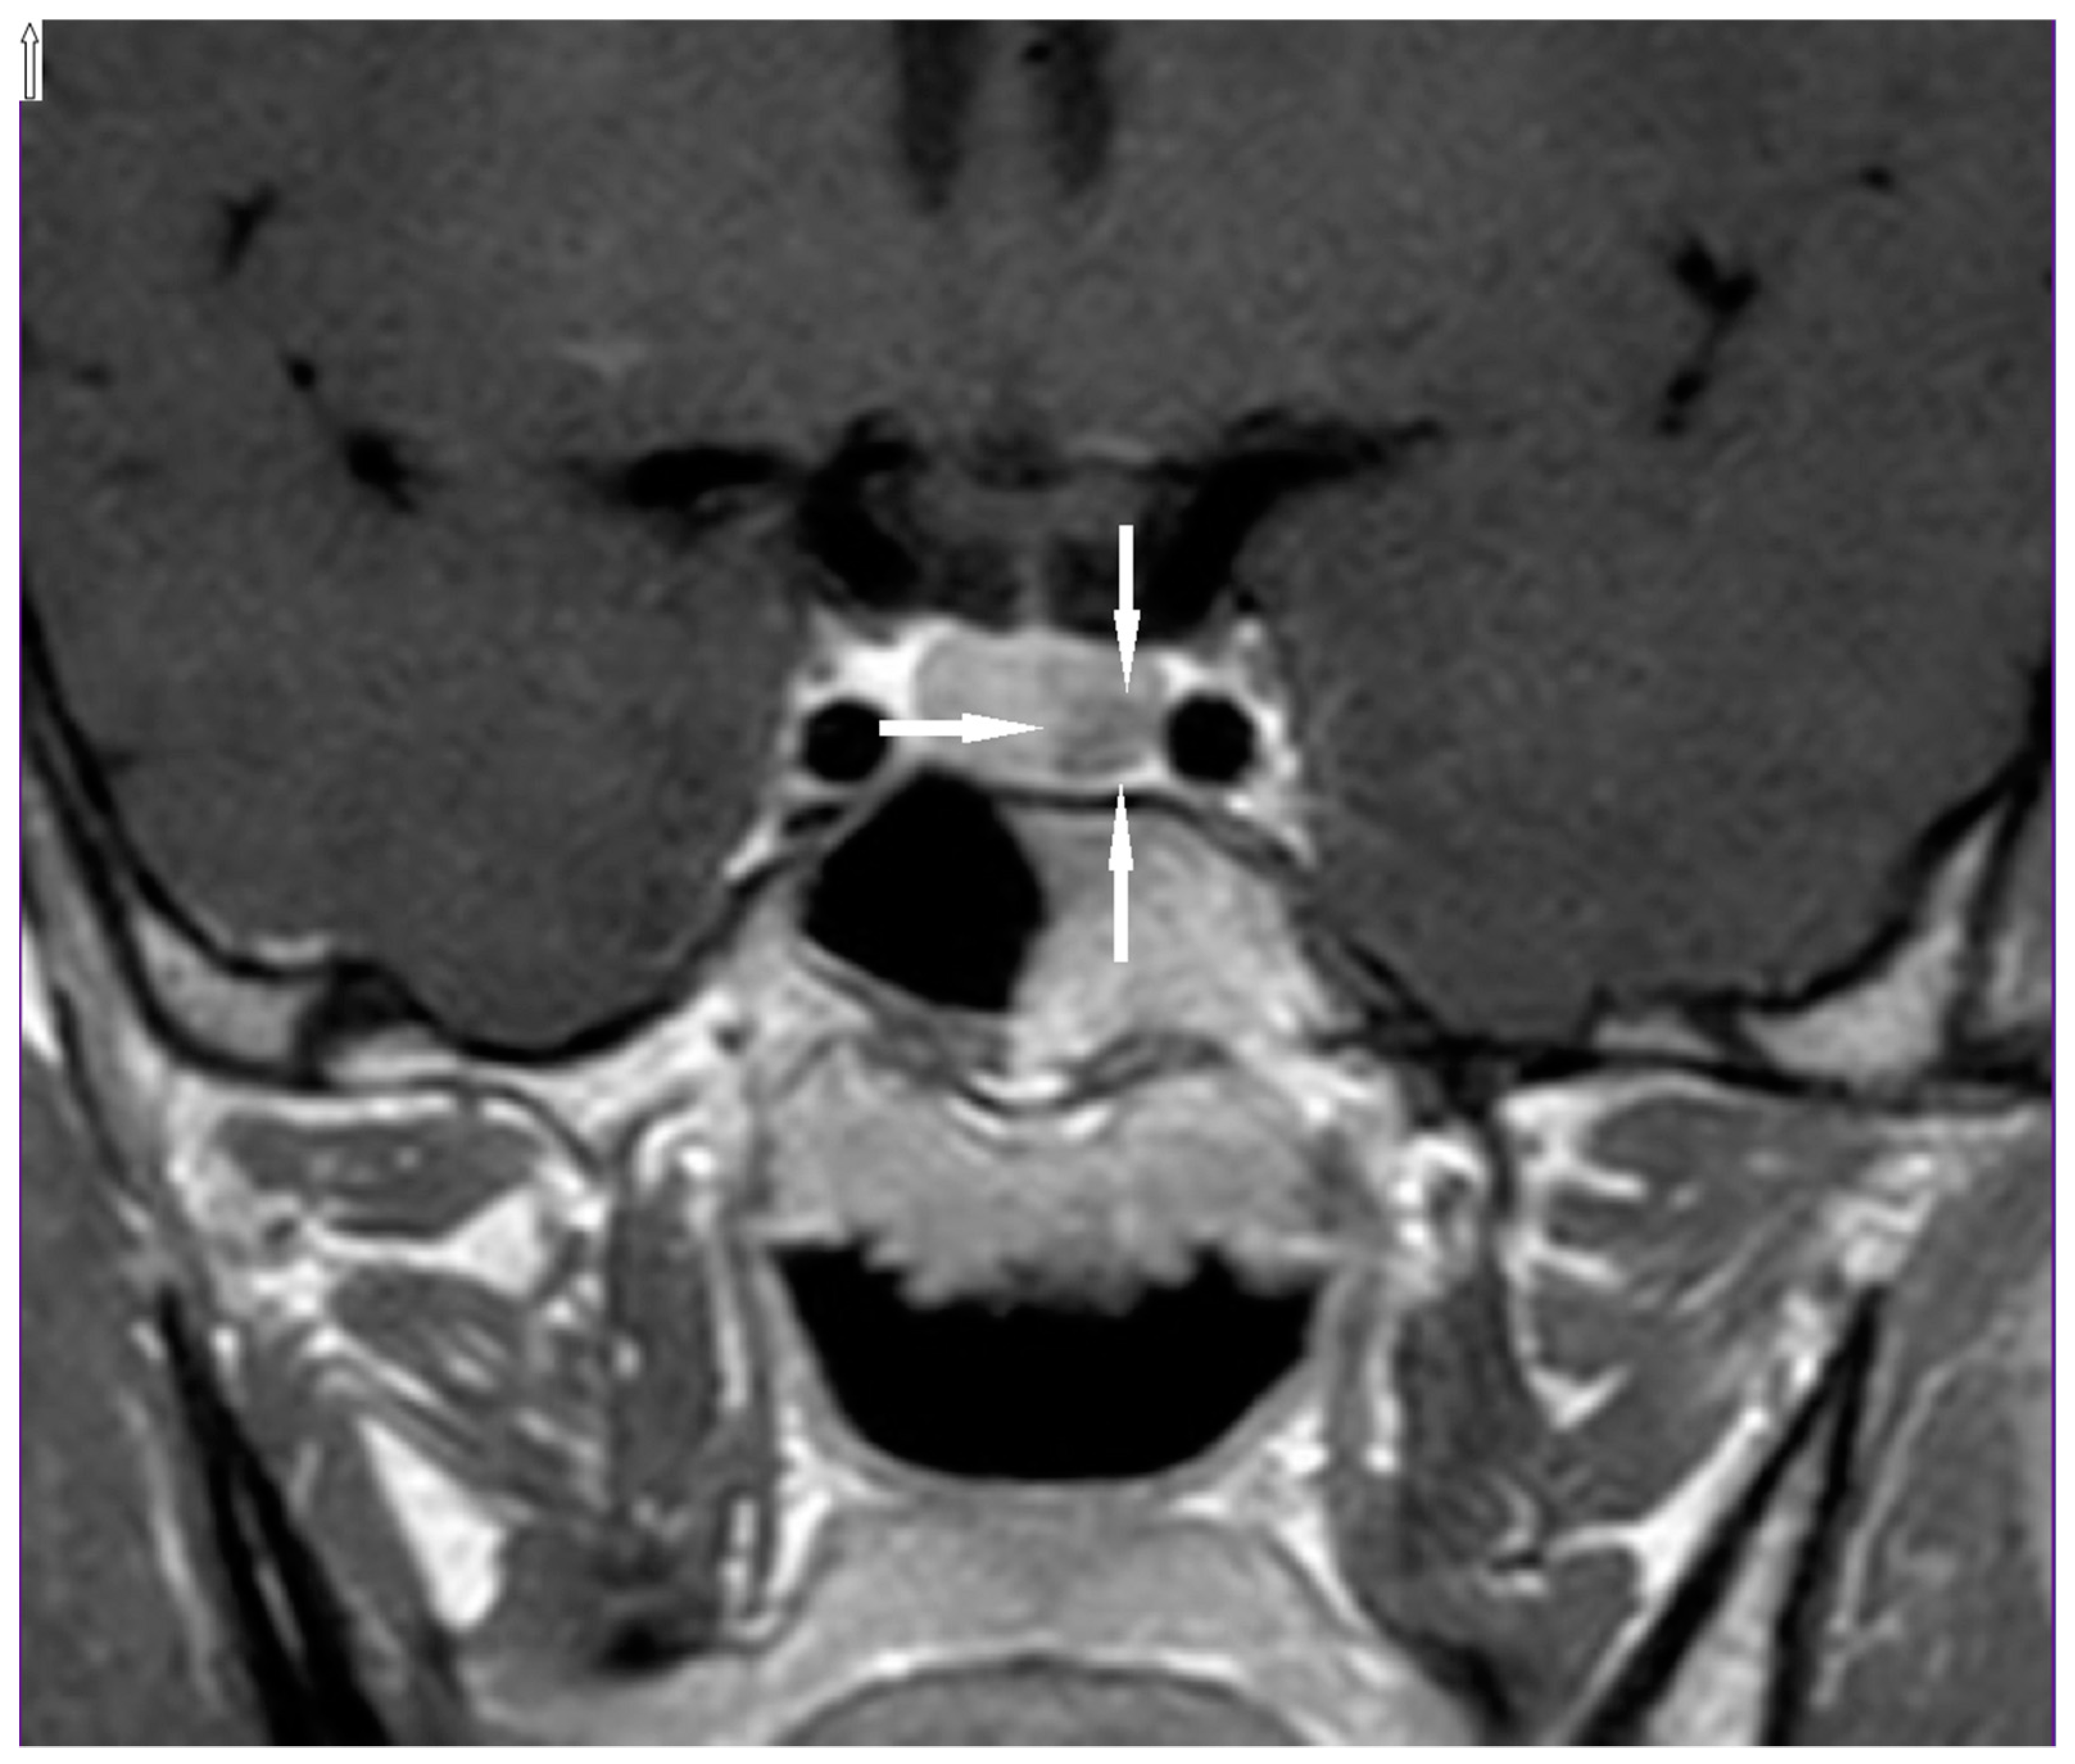

On admission to our department, a physical examination did not reveal any abnormalities. In a thyroid ultrasound examination (US), a hypoechogenic structure 5x4x8 mm was detected below the left thyroid lobe (Figure 1). An ultrasound-guided fine-needle aspiration biopsy (FNAB) was performed and confirmed the presence of a left inferior parathyroid adenoma, both cytologically and by measurement of PTH in the FNAB needle washout. Due to the young age of the patient, screening for endocrine tumors was performed and a pituitary magnetic resonance imaging (MRI) showed a lesion corresponding to a microadenoma (Figure 2). Serum prolactin and other pituitary hormonal parameters were within the normal ranges. Non-functioning pituitary adenoma was diagnosed. In accordance with the guidelines and literature data, the patient was referred to MEN1 germline mutation testing. A never-before-reported heterozygous germline mutation c.105_107dupGCT was detected, so all first-degree relatives were tested to confirm the pathogenicity of this variant.

Figure 2.

Pituitary microadenoma (arrows) visible in the MRI of the proband.